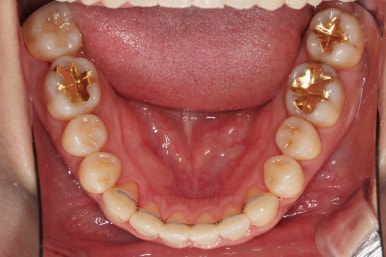

임플란트 보철이 깔끔하게 들어갔고, 교정치료도 마무리가 되었습니다.

화살표 부분은 임플란트가 안들어갔는데요.

약간의 우여곡절이 있긴했었지만 엄밀히 따지면 위아래가 지그재그로 껴들어가는 교합의 특성상 윗니는 1개 모자라도 교합에는 크게 문제가 없답니다.

해당 부분을 임플란트를 해주면 좋겠지만 환자분도 충분히 고민 후에 원하실 때 식립을 하기로 마무리르 하였습니다.

부산연산동치과 전후 사진을 비교해 보겠습니다.

총 22개월 걸렸고, 임플란트는 1개로 마무리를 했습니다.